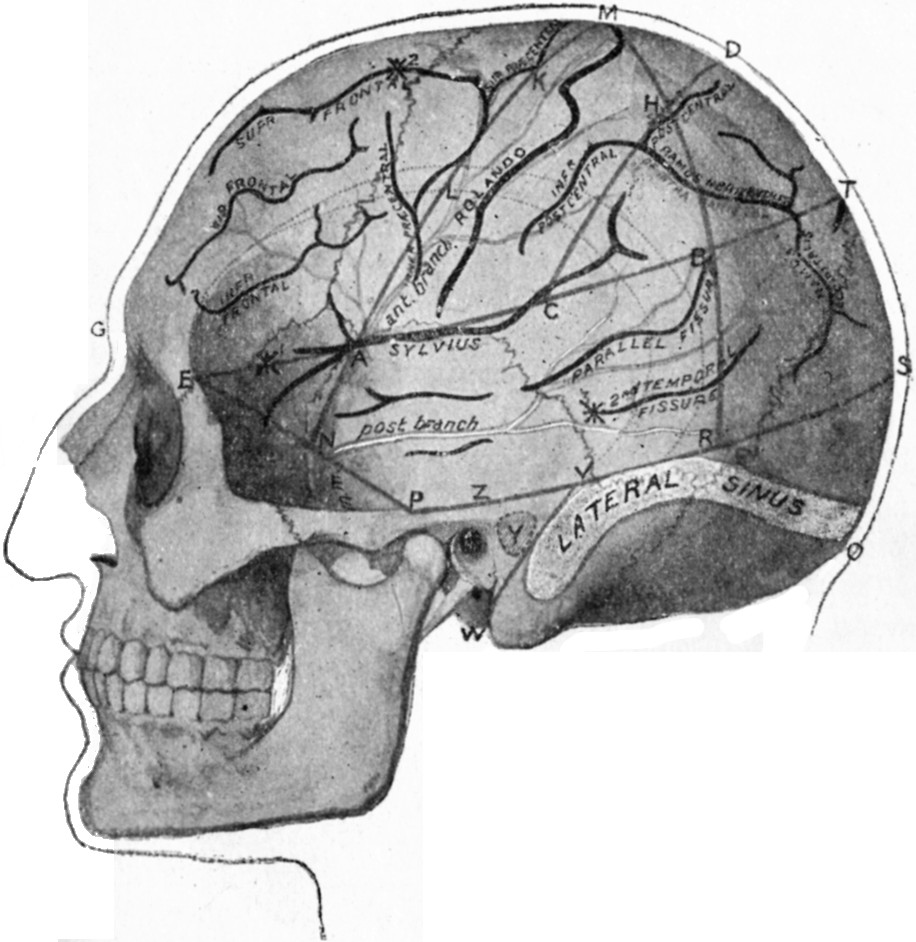

179.Relations of the Motor and Sensory Areas to the Convolutions and to Chiene's Lines330

180.Diagram of the Course of Motor and Sensory Nerve Fibres333

181.Chiene's Method of Cerebral Localisation336

182.To illustrate the Site of Various Operations on the Skull337

183.Localisation of Site for Introduction of Needle in Lumbar Puncture338